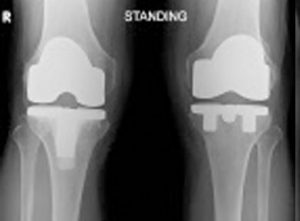

TOTAL KNEE REPLACEMENT

REVISION KNEE REPLACEMENT